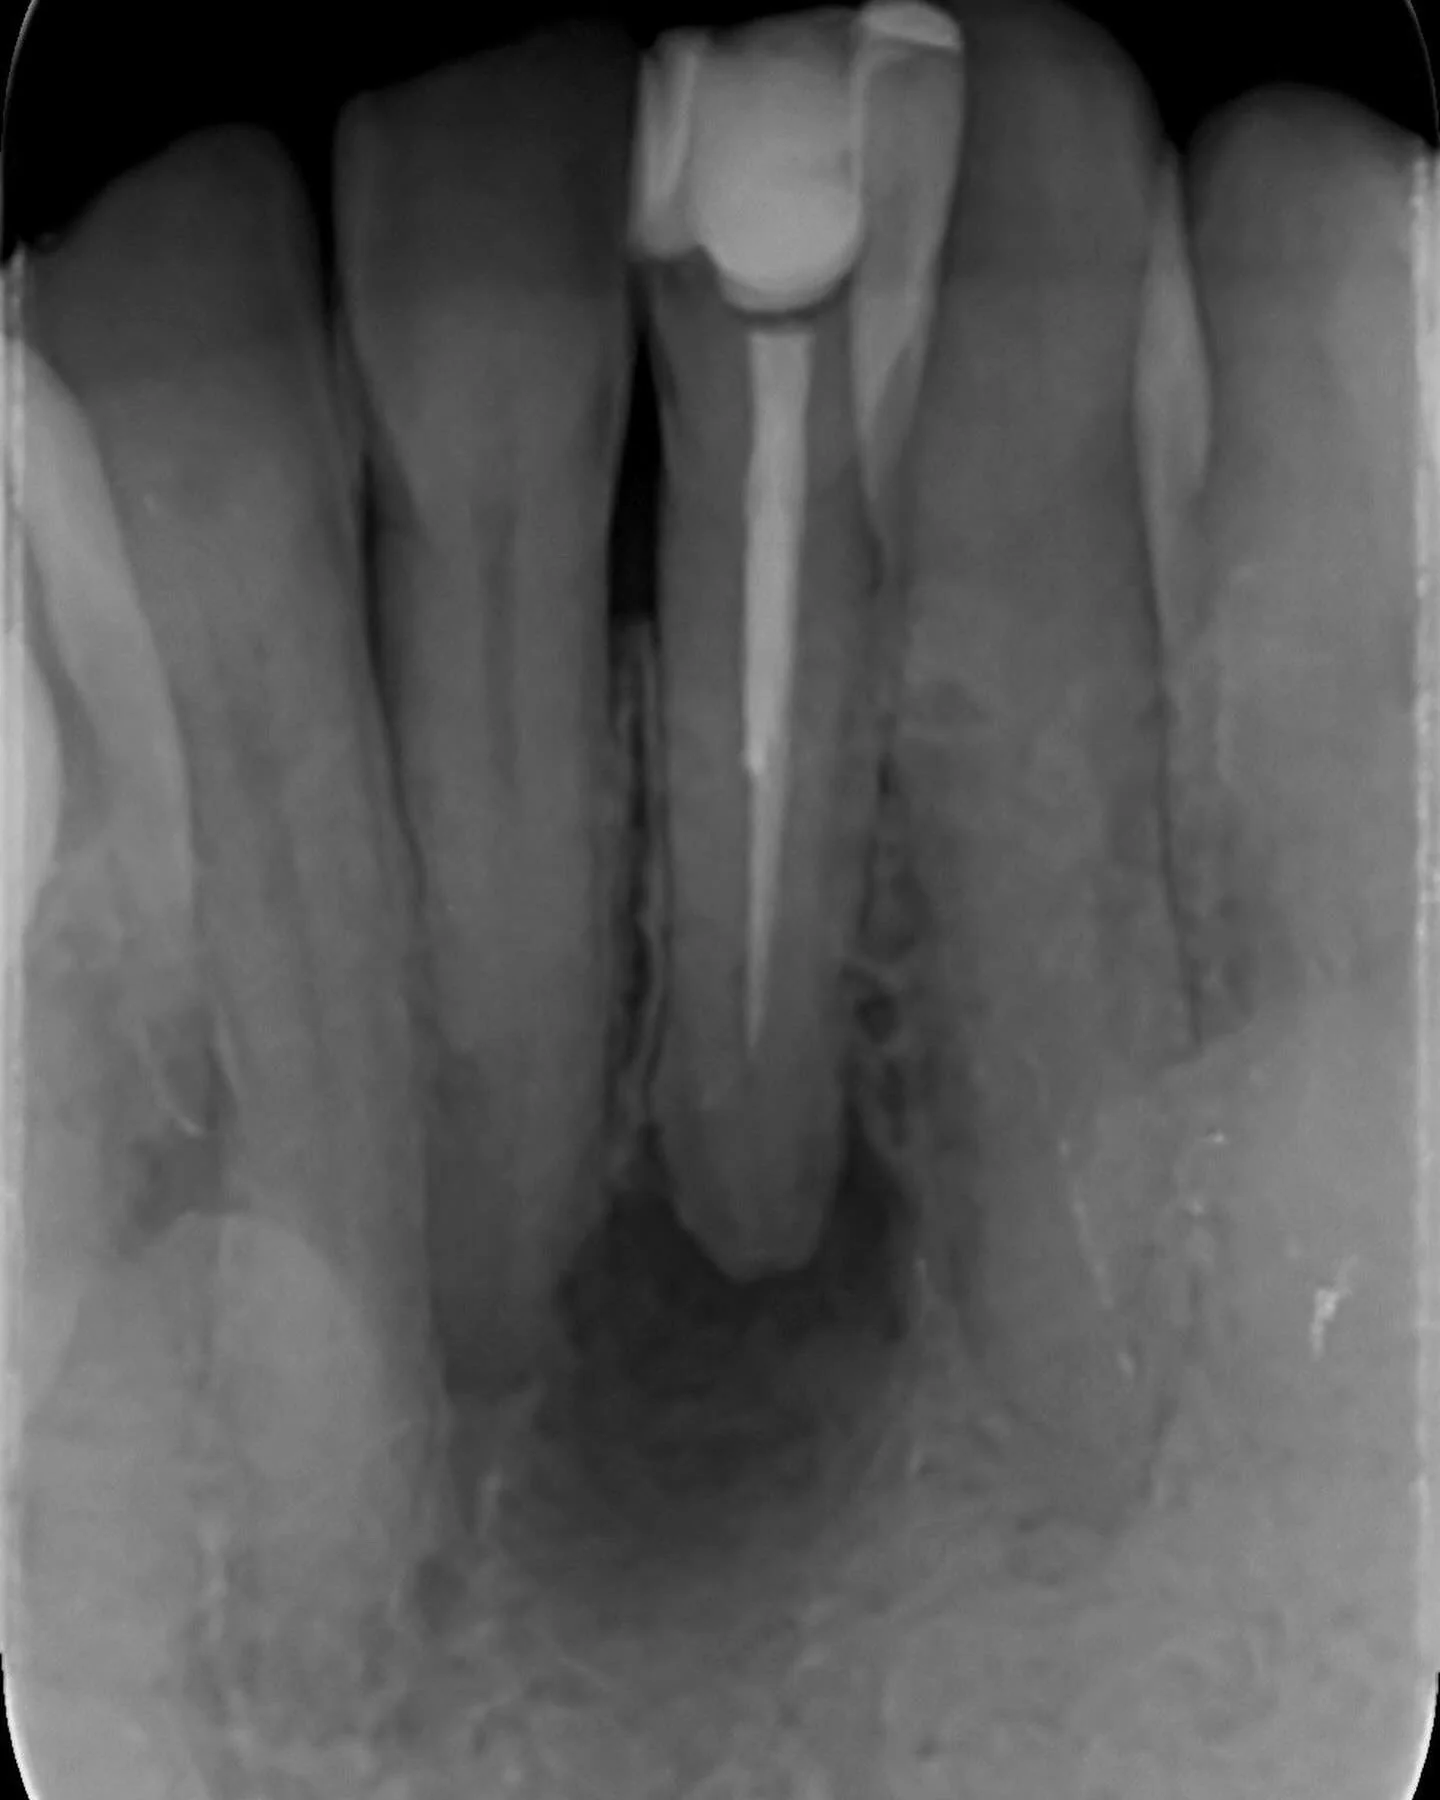

Re-treating failed root canal

Sometimes old root canal treatments can fail. In this case, the patient found her tooth was going darker. On further inspection we located and root canal treated an extra canal. This improved the tooth colour and resulted in good healing at review.